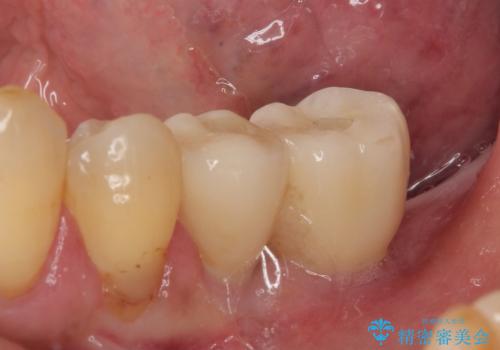

- 連結されている奥歯がグラグラしていて、インプラント治療を希望して来院された患者様です。

連結の手前の歯は歯根が破折して、クラウンが歯から外れており、奥の歯は動揺により歯根周辺の骨が吸収している状態でした。